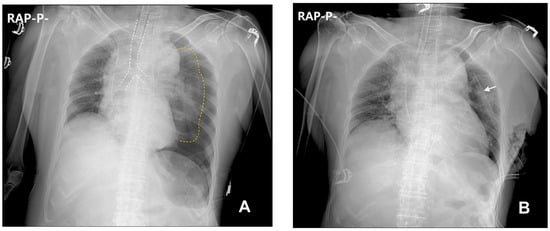

2. Case Description